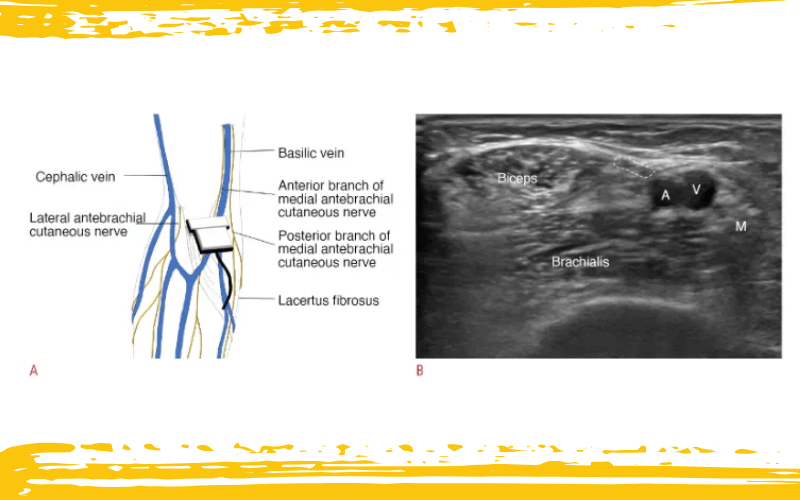

Representación esquemática de la anatomía, la colocación del transductor y la imagen ecográfica correspondiente del nervio cutáneo antebraquial medial en el codo derecho.

A. El nervio cutáneo antebraquial medial discurre junto a la vena basílica y medial al músculo bíceps, que puede utilizarse como referencia anatómica para localizar el nervio.

B. La imagen ecográfica correspondiente muestra el músculo bíceps braquial (Bíceps), el braquial, la vena braquial (V), la arteria braquial (A), el nervio mediano (M) y la rama anterior del nervio cutáneo antebraquial medial (línea discontinua).